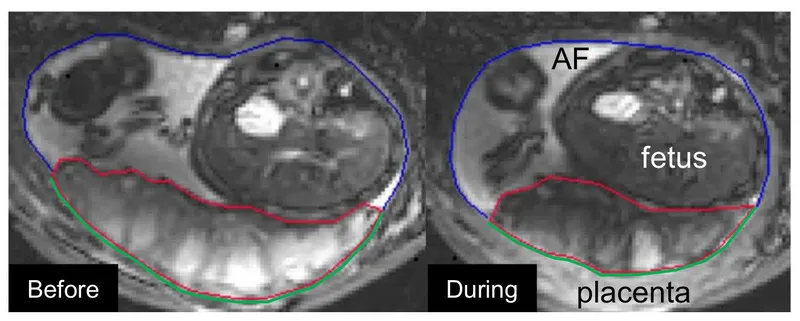

Placenta Dataset

The Placenta dataset comprises 21 3D MRI images. This dataset is unique to the University of Nottingham and is essential for studying fetal pathology through placental analysis. The scarcity of data presents a significant challenge, making robust model performance critical.